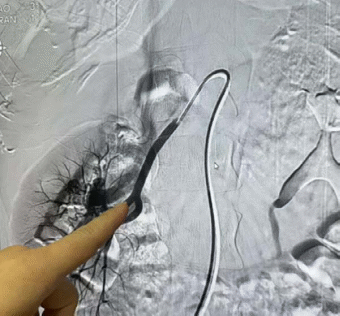

患者治疗影像

入院后,患者再次出现严重血尿,泌尿外科团队迅速组织讨论,结合患者病史及临床表现,初步判断为动静脉瘘可能性较大。为尽快控制出血,泌尿外科立即与介入科取得联系,共同制定治疗方案。6月20日,在介入科的协助下,患者成功接受了急诊介入栓塞术,术中出血迅速得到控制,术后患者恢复良好。